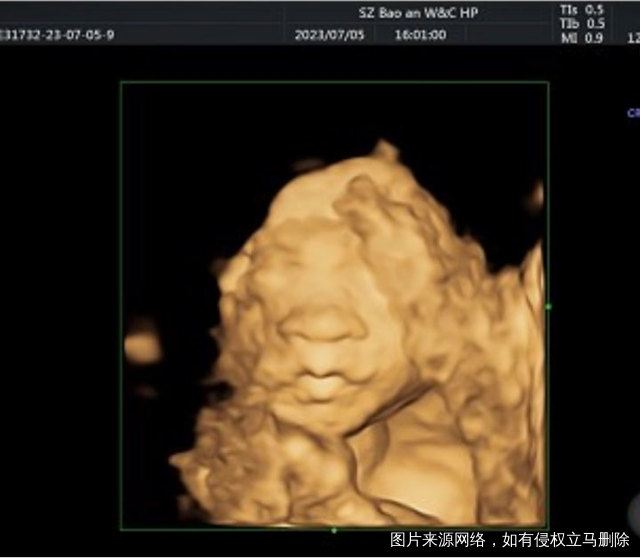

我是在深圳中山泌尿外科医院做的试管,后面过了九周就转到了宝安妇幼建档了,一路上也是披荆斩棘过来的,一直在保胎。